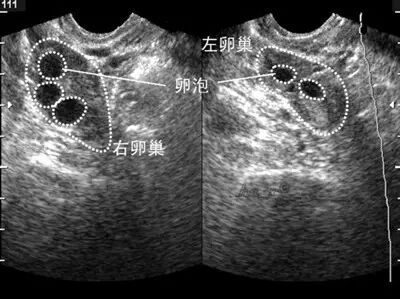

☆☆通过B超来判断是否多囊卵巢综合征的标准:1、卵巢增大(卵巢体积≥10ml)、变圆、包膜增厚。2、一侧卵巢内有10-12个小卵泡,直径在2-9mm,呈车轮状排列。

☆☆一个成熟的卵泡是>10mm的,医学上称为优势卵泡;小卵子只有成为优势卵泡才表明其正常发育。此时是女性月经周期一周左右,然后优势卵泡继续发育,每天增长2-3mm左右,直至20mm左右预示会排卵。因此多囊卵巢综合征的姐妹会有许多小卵泡但这些卵泡不会继续发育,也就不能排卵,没有卵子与精子结合而不会怀孕了。